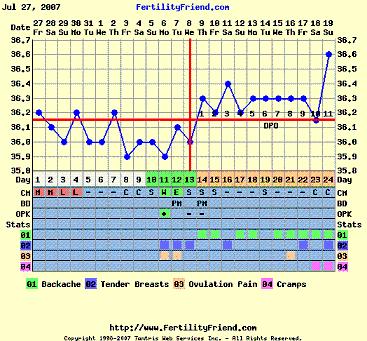

Ha valaki nem tudná "kiolvasni", mit lát, segítek: az első képen a drágánk feje jobb ldalt (a másikon is

) , aztán a kis teste, a cicije felett a pici folt az egyik keze, aztán egy nagy pocak, majd valahogy a lábai (egy pár lábujjacskája látható!

)

A másik képenközelebbről van a buksija, lehet látni a nóziját, meg az éppen csókra álló száját!!

Ja, és amikor uh-zott a doki, kitátotta a száját, vissza is játszotta BB, mondta, hogy tök érdekes, még ilyen pici, és nyitogatja a száját! Hát egész nap vigyorogtunk, úgy örültünk! Tényleg nagyon jó volt látni!

Ő a kisfiúnk, csak így tudtuk lefotózni, ennél jobban nem mutatta a kis pofiját.

Ő a kisfiúnk, csak így tudtuk lefotózni, ennél jobban nem mutatta a kis pofiját.